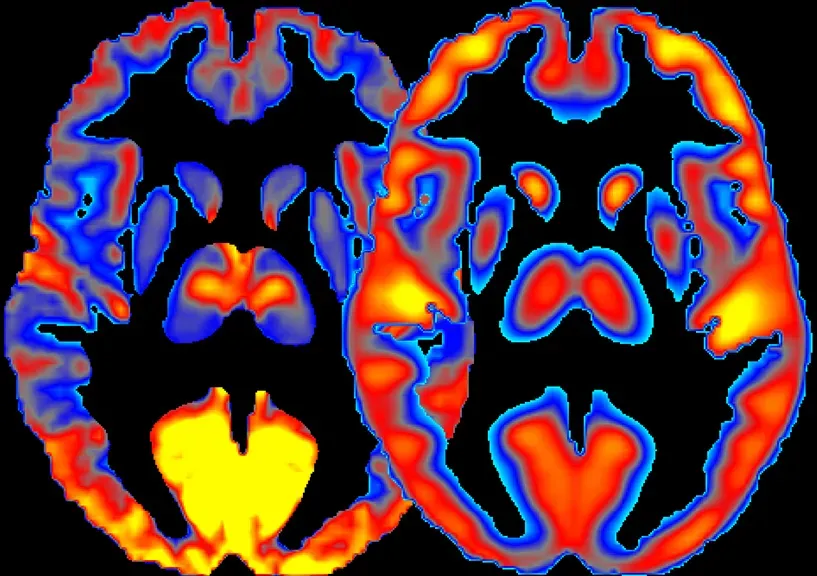

Neuroimaging highlights amygdala and hippocampal hyperactivity alongside prefrontal cortex hypoactivity, elucidating the emotional vividness and cognitive disorganization of dreams. Your emotional centers are firing on all cylinders while your logical brain takes a break. No wonder dreams feel so intensely real yet utterly illogical.

Studies suggest the amygdala, which plays a role in emotional processing, appears to be very active during dreaming, and areas of the brain involved in visual processing are active during dreaming. Meanwhile, parts of the brain involved with our ability to plan, think through things and apply logic and order are less active during dreaming. This neural choreography explains why you can dream vividly about impossible scenarios without questioning them.